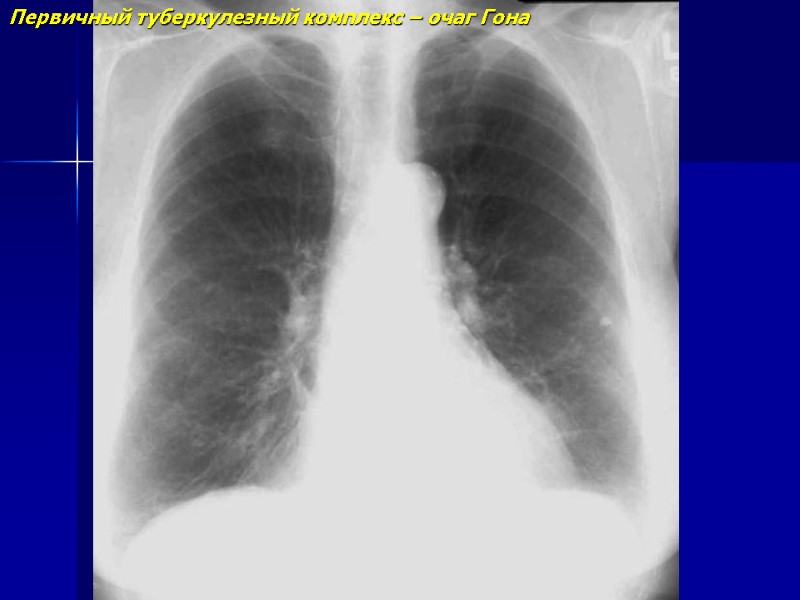

Первичный туберкулезный комплекс – очаг Гона